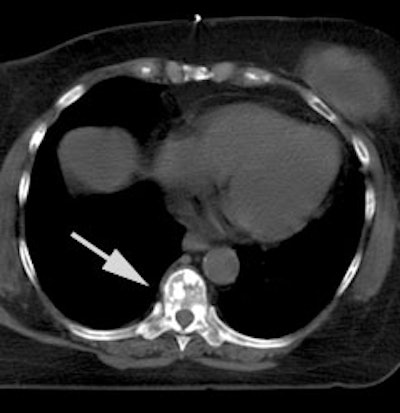

Breast cancer with sclerotic bone mets: The patient below was found to have extensive sclerotic bone metastases on bone scan (left image) and CT (white arrow). Note the lack of tracer uptake on the patient's PET scan (right images). PET is less sensitive for the detection of sclerotic bone metastases, but is superior to bone scan for the detection of lytic lesions. |

|